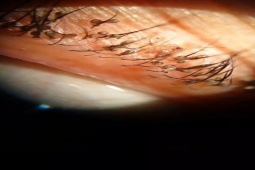

BSCKI Nguyễn Thị Hòa, chuyên ngành Da liễu, Trung tâm Khám, điều trị theo yêu cầu và Quốc tế, cho biết qua thăm khám, các bác sĩ phát hiện tại vùng mu của bệnh nhân có nhiều dát màu xanh sáng, kích thước khoảng 1-2 mm, kèm theo các sẩn nhỏ và nhiều vết xước do cào gãi. Kết quả soi da dưới kính hiển vi cho thấy hình ảnh rận mu (Pthirus pubis) di chuyển trên từng sợi lông, thậm chí quan sát rõ một cặp rận đang bám chặt vào nhau.

Người phụ nữ được thăm khám trong tình trạng quanh mí mắt bị ngứa, cộm, sưng đỏ và chảy nước mắt. Dưới kính hiển vi, các bác sĩ phát hiện bầy rận mu đang ký sinh trên mí mắt, đẻ trứng chi chít lên lông mi người bệnh.